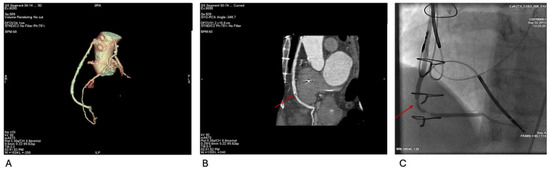

Figure 5A–C demonstrate anomalous LCx anatomy with significant stenosis and corresponding CT-FFR values, underscoring the added value of physiology-based interpretation for guiding therapy.

Figure 5.

(A) Volume-rendered CCTA shows the left circumflex artery (LCx) originating from the proximal right coronary artery (RCA) and coursing retro-orbitally toward the left atrioventricular groove (arrow). (B) Curved-planar reconstruction depicts a severe (>70%) mixed-plaque stenosis in the proximal anomalous LCx (arrow); the ostial segment is normal in caliber. (C) CT-derived fractional flow reserve (CT-FFR) demonstrates preserved values (≥0.80) proximal to the area of stenosis, followed by a drop to <0.80 across the stenosis, indicating physiologic significance.